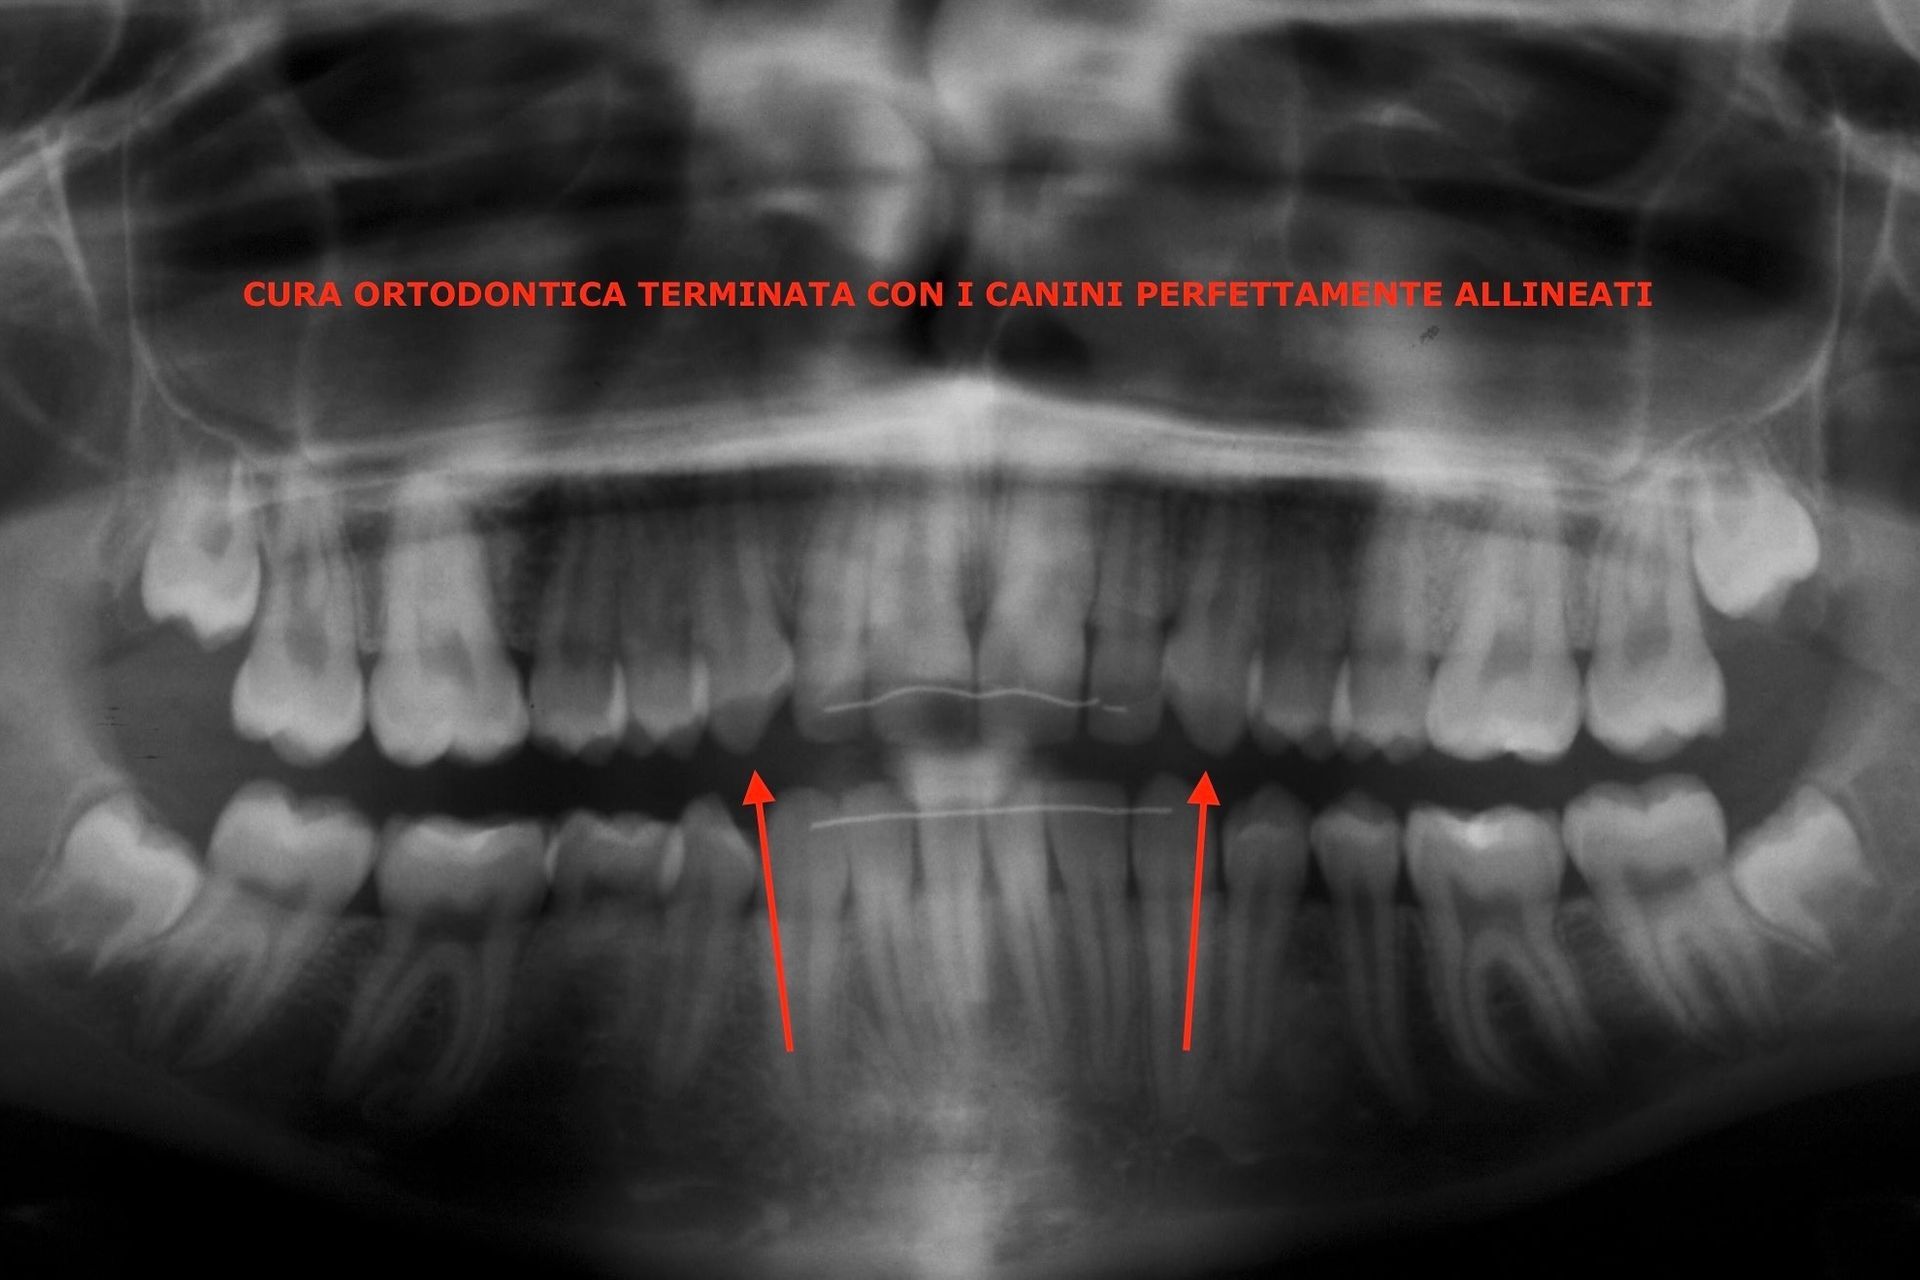

Cura ortodontica terminata con i canini perfettamente allineati

Canino incluso

Posizione orizzontale del canino

Rimozione chirurgica del canino incluso

Risultato finale